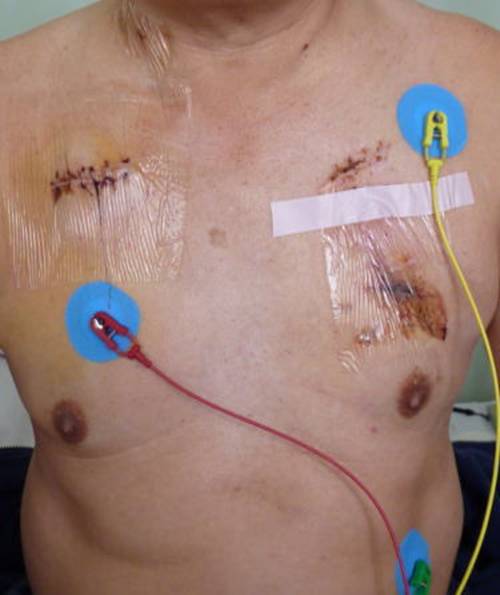

この記録は次の画像から始まる。

201201012349

201201231149手術前

201201241322手術前